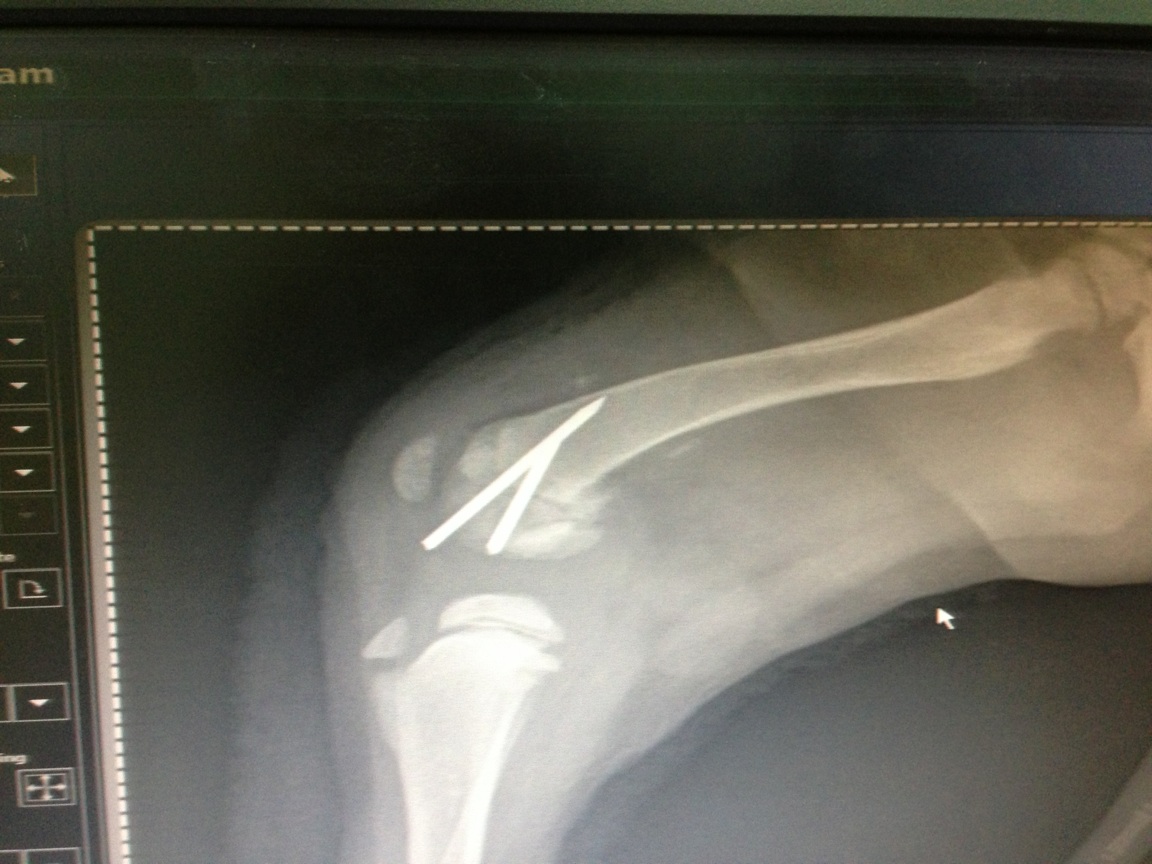

Distal Radius Fracture in back right leg when it was ran over in a “Hit & Run” accident last Friday evening in Rawang. (Attached Image 3 as the X-ray)Healing Treatments:

A) To undergo Percutaneous Pinning surgery and input a cross pin onto the fractured part. This will be done by the vet you recommended.

The vet also texted over the following photos: